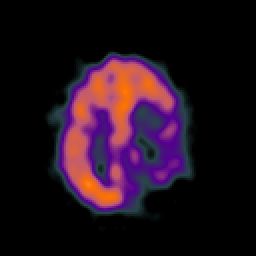

SPECT TC Study #4 -- Slice #39

[Home][Help][Clinical][Tour 1][Tour 2][Tour 3] Slice 39